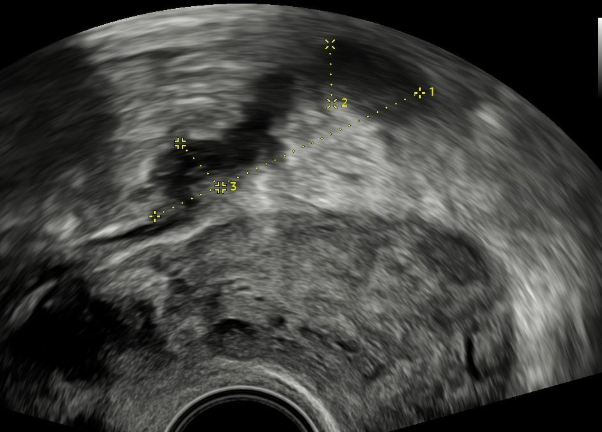

Rozsáhlá endometrióza tlustého střeva.